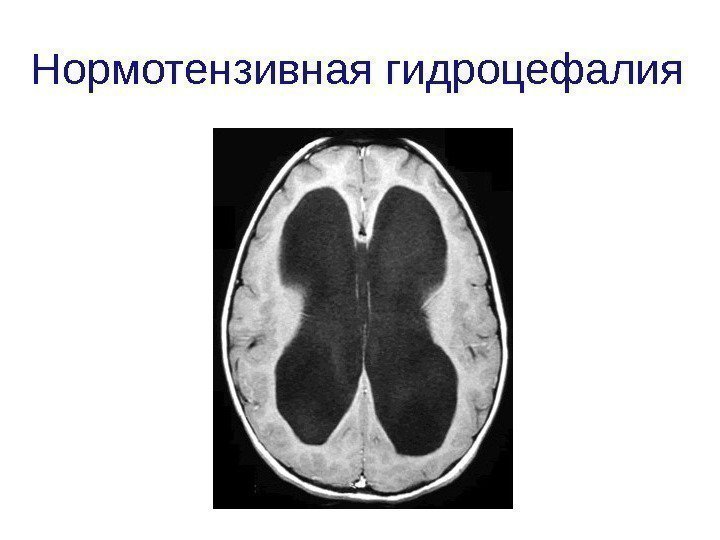

Признаки умеренно выраженной наружная

Признаки умеренно выраженной наружная 113 фото